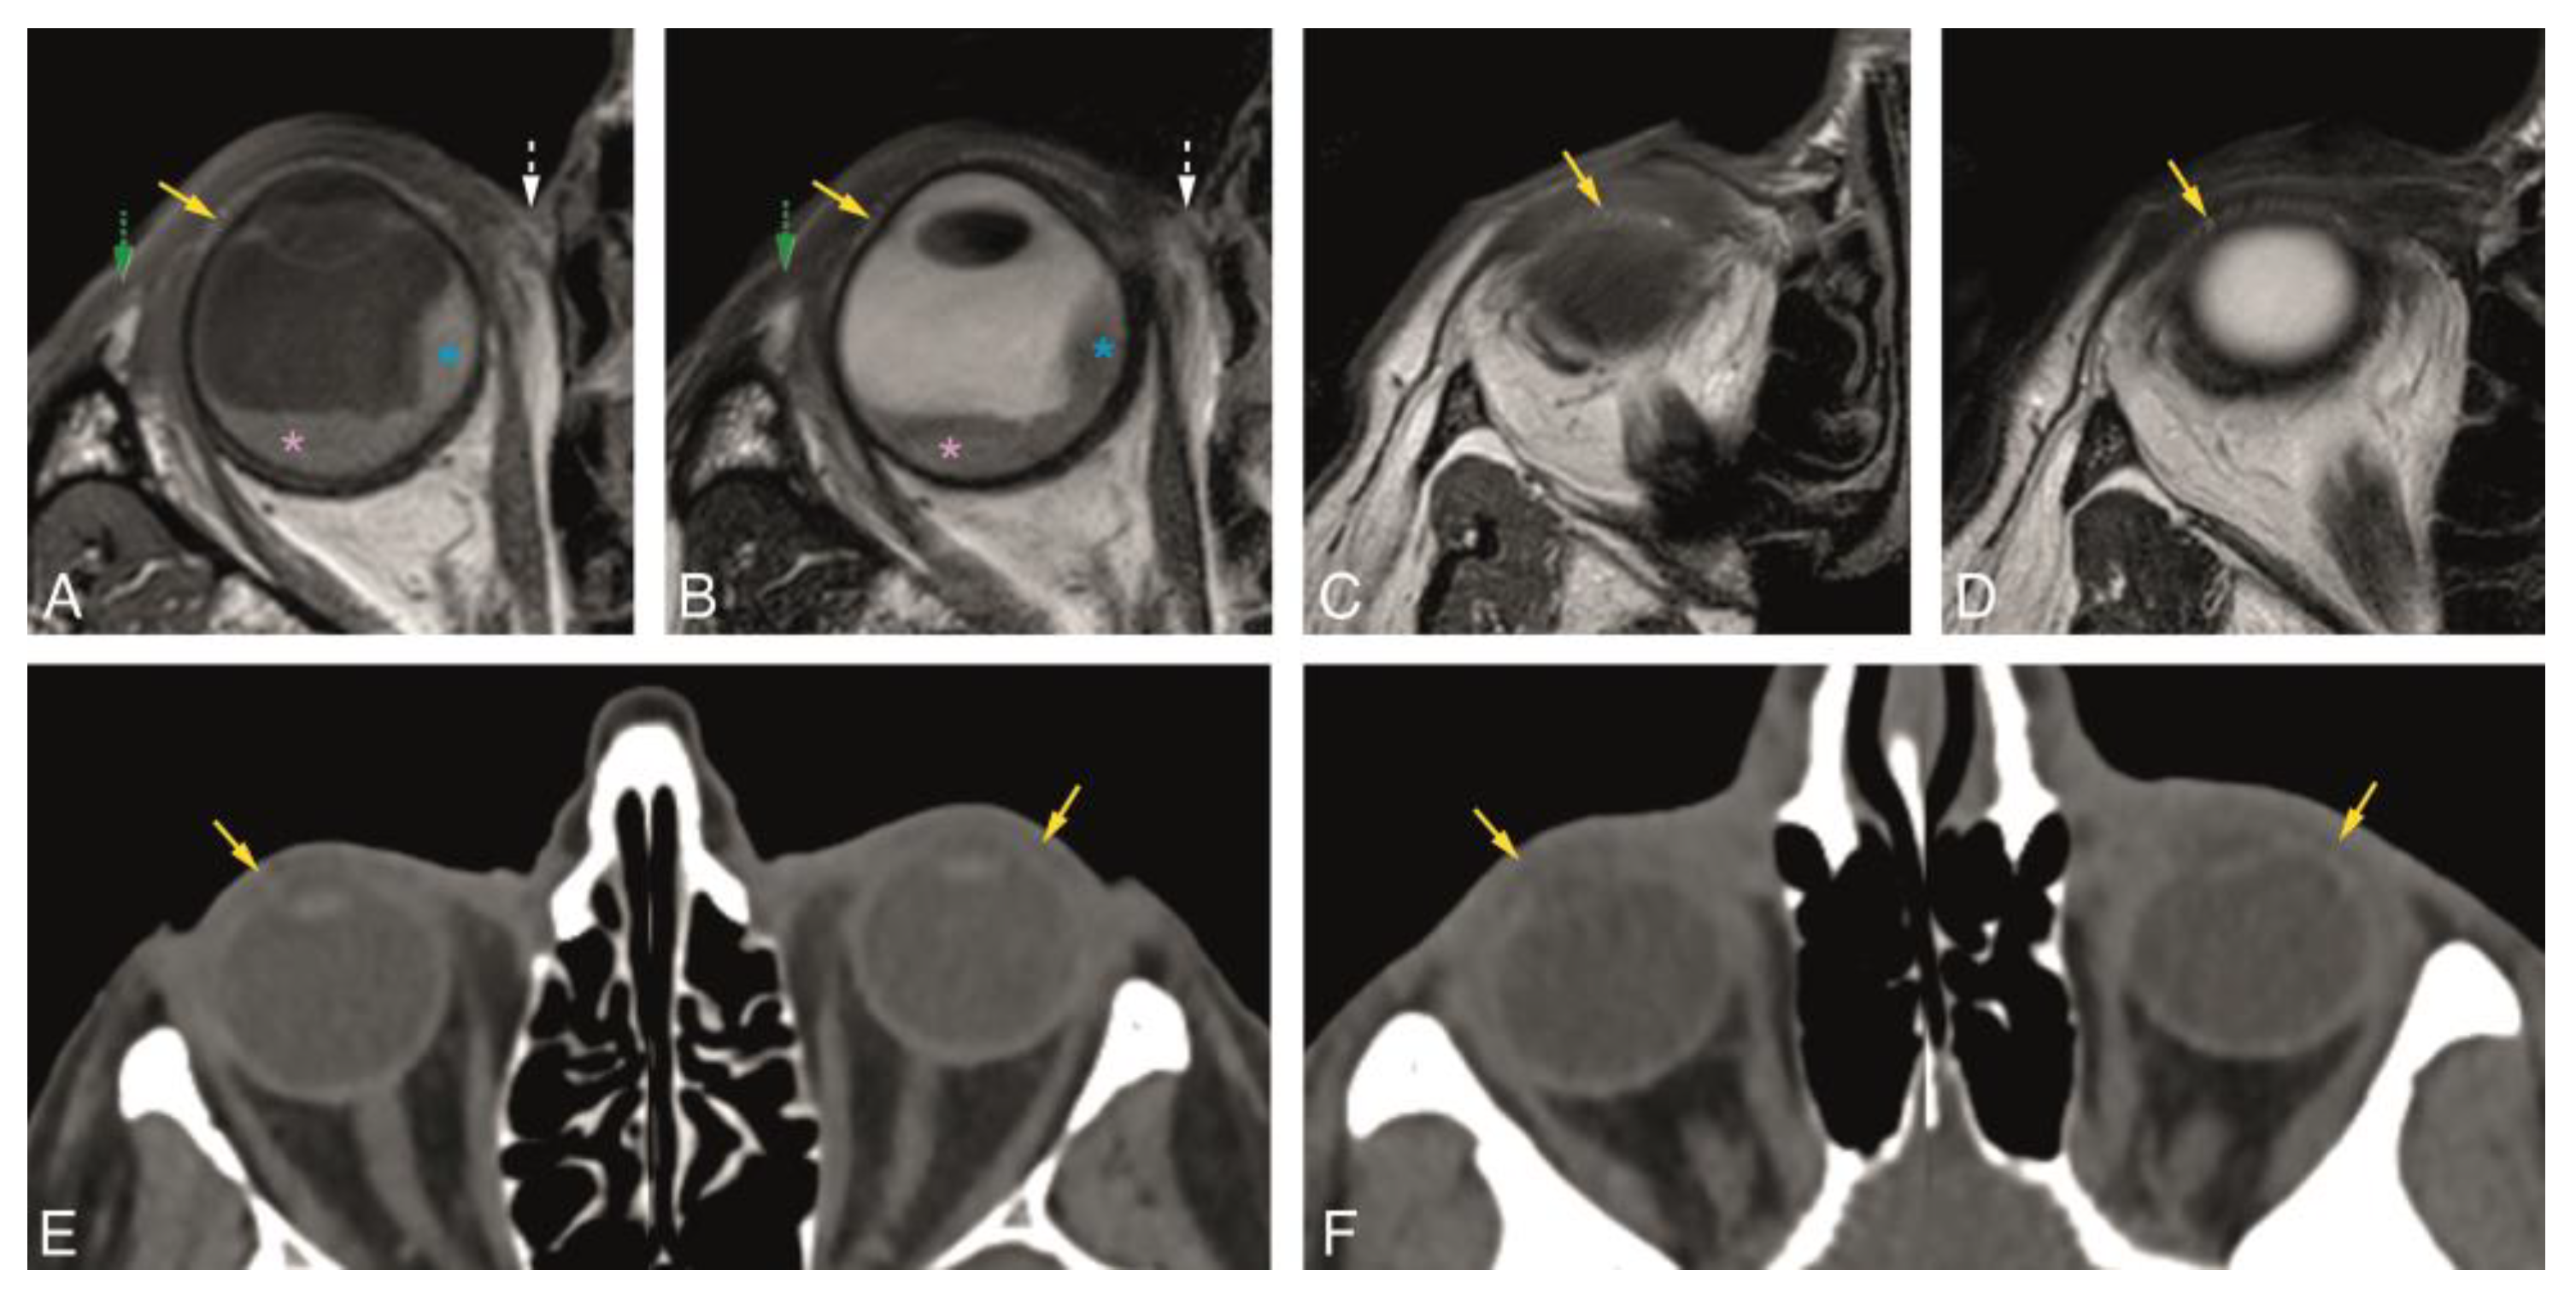

Figure 3. A, B, and E: Normal superior tarsal plate (yellow arrow) on the axial plane on MR T1-WI (A), T2-WI (B), and on CT (E). Notice, at A and B, the uveal melanoma (blue asterisk) with associated retinal detachment (pink asterisk), impossible to differentiate on non-contrast enhanced sequences. C, D, and F: Normal inferior tarsal plate (yellow arrow) on the axial plane on MR T1-WI (C), T2-WI (D), and on CT (F). Yellow arrow: superior and inferior tarsal plates; green dashed arrow: lateral palpebral ligament region; white dashed arrow: medial palpebral ligament region; blue asterisk: uveal melanoma; pink asterisk: retinal detachment.

In Group 1, the visibility of the superior and inferior tarsal plates and orbital septa was scored on MRI (Table 1). Both the superior and inferior tarsal plates were identifiable in 94% of the subjects, being the superior tarsal plate well-defined in 78% and the inferior tarsal plate well-defined in 67% of the subjects. The superior tarsus was easier to identify on the axial plane. The inferior tarsus was equally well visible on the axial and sagittal planes (Figure 2A,E,F, and Figure 3A–D). The superior septum was always visible, being well-defined in 92% of the subjects. The inferior septum was visible in 91% of the subjects, but it was well-defined in only 36% of the subjects. The superior and inferior septa were easier to identify on the sagittal plane (Figure 2A,B,E,F, and Figure 4A–D). Orbital septa and tarsal plates were more difficult to identify when the slices were not acquired perpendicular to the main axis of the eyelid, and when movement artifacts were present. In Group 2, and similarly to Group 1, the superior and inferior tarsal plates and orbital septa were scored (Table 2). The superior tarsus was always visible, being well-defined in 63% of the subjects. The inferior tarsus was visible in 84% of the subjects and was well-defined in 53% of the subjects. Both the superior and inferior tarsal plates were better depicted on the axial plane than on the sagittal plane (Figure 2G and Figure 3E,F). The superior septum was visible in 89% of the subjects and well-defined in 47% of the subjects. The inferior septum was visible in 68% of the subjects, but well-defined only in 11% of the subjects. The superior and inferior septa were easier to identify on the axial plane (Figure 2C,G and Figure 4E,F) than on the sagittal plane.